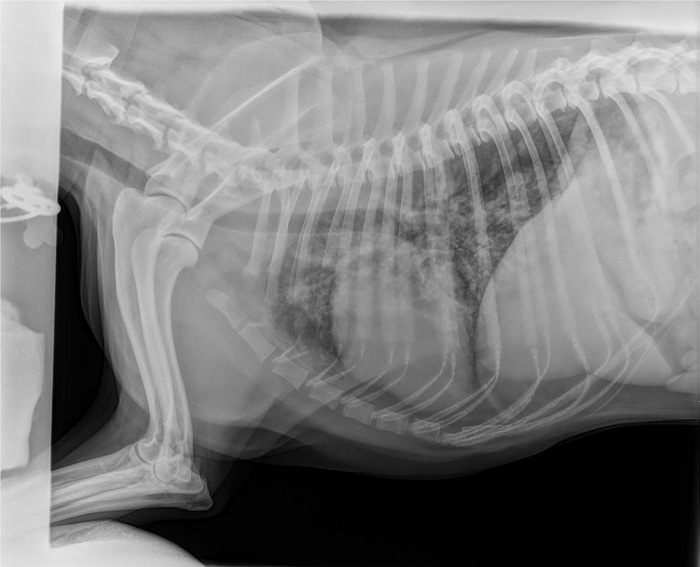

Дано: возрастная кошка с длительным ринитом.

Пришли на прием 13.10 с формулировкой «гноится глазик». Я увидел их 14.10 и всё же уговорил пойти на кт, а там абсцесс за левым глазом, фронтит (забиты и лобные пазухи, и носовые ходы).

После проводим фронтотомию - по сути, бурим дырку в лобную пазуху для промывания и вымывания всего скопившегося гноя.

Промыв всё большим количеством тёплого стерильного физ.раствора, зашиваем всё. Плюсом удаляем назофарингеальный полип.